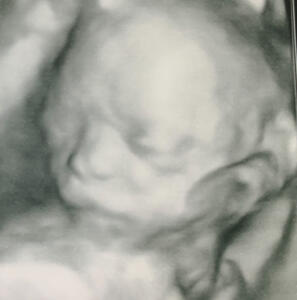

LA OBESIDAD DISMINUYE LAS PROBABILIDADES DE REALIZAR UN DIAGNÓSTICO CORRECTO

La obesidad es un factor que disminuye la sensibilidad del diagnóstico de ciertas patologías fetales. El control fetal se realiza con ecografía. Ésta se basa en la emisión y recepción de ultrasonidos. Los sonidos se distorsionan conforme aumenta el espacio sólido que hay entre lo que queremos observar y la sonda del ecógrafo. En resumen, en las pacientes obesas, la visión ecográfica de su bebé es más dificultosa y con menor resolución. Ello hace que el diagnóstico no sea tan preciso y que se puedan pasar por alto algunas alteraciones.

El peso ideal de la mujer durante el embarazo facilita las exploraciones ecográficas.

La ecografía es una técnica diagnóstica basada en la penetración de ultrasonidos a través de las capas del cuerpo. A mayor grosor de las capas menor sensibilidad de la ecografía, con imágenes más borrosas y difíciles de interpretar.